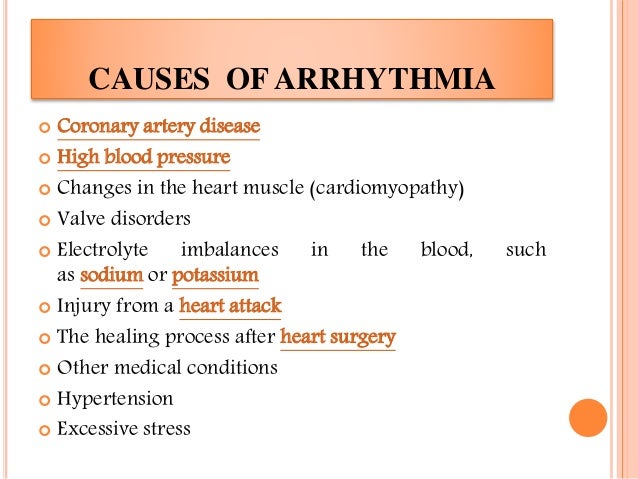

Arrhythmia : Causes, Symptoms And Treatment

www.slideshare.netArrhythmia : Causes, Symptoms and Treatment

www.slideshare.netArrhythmia : Causes, Symptoms and Treatment

10 Causes Of Arrhythmia (Irregular Heartbeat) You Must Know

curejoy.com10 Causes Of Arrhythmia (Irregular Heartbeat) You Must Know

curejoy.com10 Causes Of Arrhythmia (Irregular Heartbeat) You Must Know

Arrhythmia : Causes, Symptoms And Treatment | PPTX

www.slideshare.netArrhythmia : Causes, Symptoms and Treatment | PPTX

www.slideshare.netArrhythmia : Causes, Symptoms and Treatment | PPTX